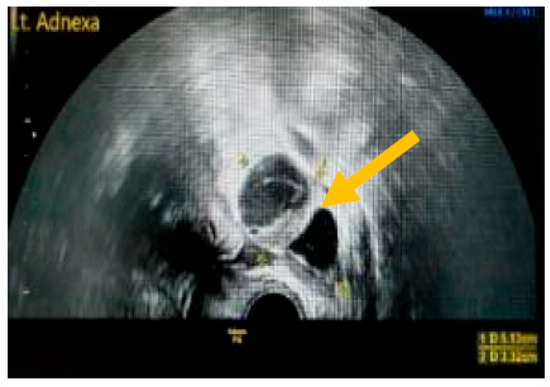

The existence of irregular solid tumors, ascites, at least four papillary structures, an irregular multilocular-solid tumor (diameter at least 10 cm), and very strong blood flow on a color Doppler assessment are malignant indicators, whereas a unilocular cyst, the presence of solid components (max diameter < 7 mm), the presence of an acoustic shadow, a smooth multilocular tumor (max diameter < 10 cm), and the absence of detectable blood flow on the Doppler predispose for the presence of a benign mass [24] (Figure 1, Figure 2 and Figure 3).

Figure 2. Multilocular solid tumor. (Yellow arrow indicates the presence of a cyst with multiple septums, measurable solid components, and papillary projections.)